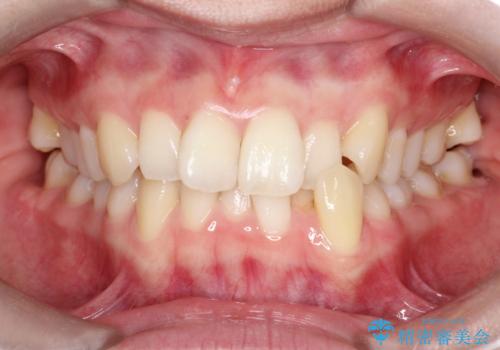

【インビザライン】 前歯の反対咬合を治したい

左下5番は先天性欠損のため乳歯は抜歯しインプラントにて欠損補綴しています。